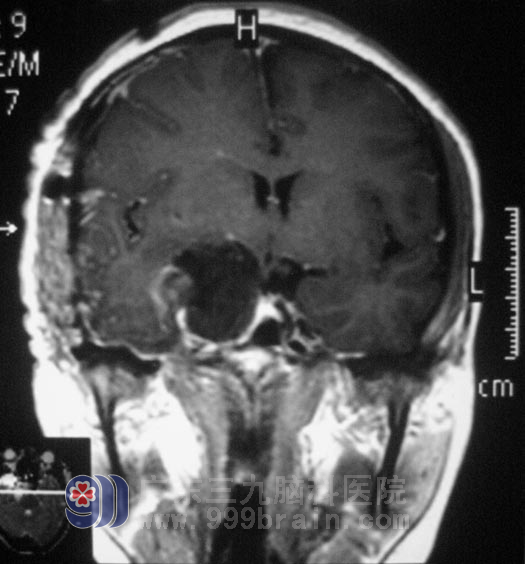

7月,李女士来到广东三九脑科医院综合神经外科就诊,鲁明主任阅片后初步判断为神经鞘瘤可能性大。完善相关检查后,7月8日,由鲁明主任主刀,在全麻下行右侧海绵窦内占位性病变切除术+颅底重建术+颅内压检测仪植入术,术中见肿瘤位于海绵窦内,色白,质韧,边界清楚,肿瘤包绕动眼神经。在显微镜下切除肿瘤,整个手术过程顺利。病理结果为:(海绵窦内)神经鞘膜瘤。术后李女士顺利渡过出血、感染、水肿期,已办理出院手续。

▲手术后